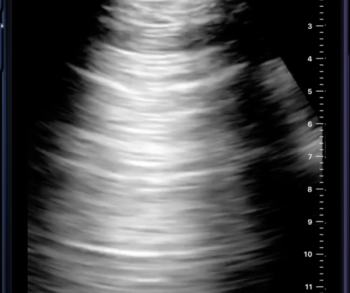

In order to facilitate optimal detection and assessment of liver fibrosis and steatosis, the newly launched Hepatus 6 Diagnostic Ultrasound System offers the capabilities of real-time two-dimensional ultrasound with visual transient elastography in one device.